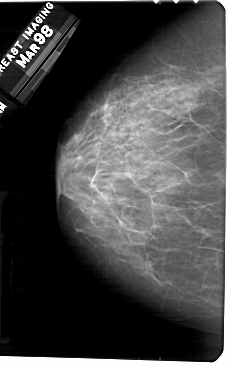

A_1363_1.LEFT_CC

LEFT_CC LINES 5491 PIXELS_PER_LINE 3391 BITS_PER_PIXEL 12 RESOLUTION 43.5 NON_OVERLAY